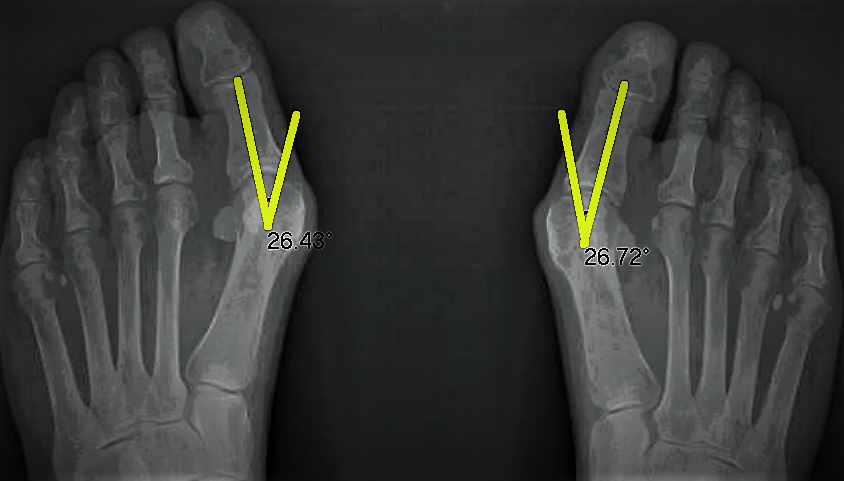

As we do with all our bunion corrections, we sent Lorraine for a follow up x-ray to measure her results. Lorraine’s bunions had reduced by over 10 degrees, which is a huge improvement. The great news is that with minimal ongoing treatment, we will be able to further straighten the bunion until there is no deviation.